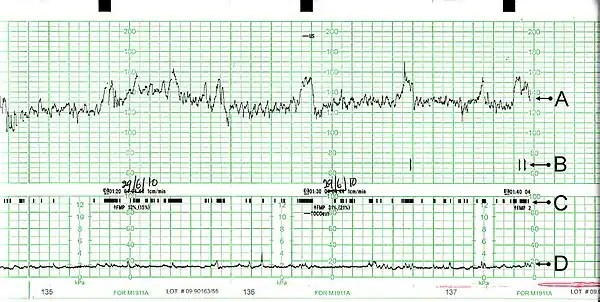

A: Los latidos del corazón del feto; B: Indicación que muestra los movimientos que siente la madre (debida a la presión de un botón); C: El movimiento fetal; D:Las contracciones uterinas